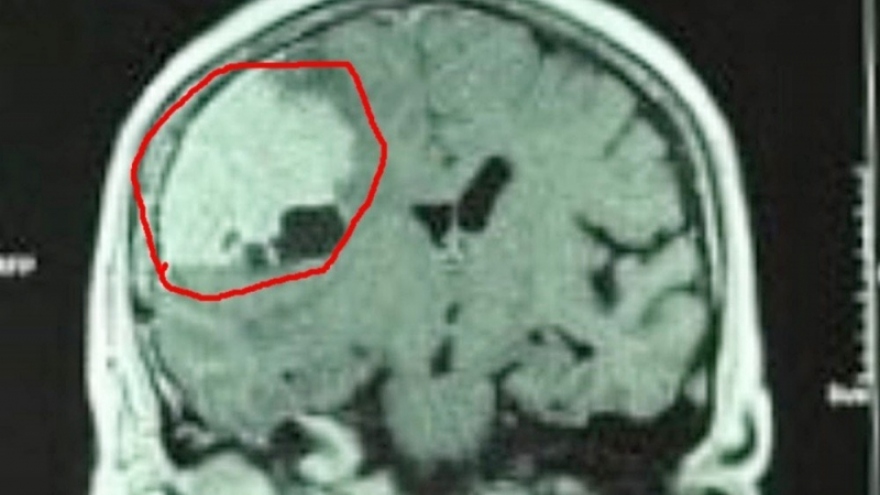

VOV.VN - Mỗi lần xuất tinh, người đàn ông lại bị đau đầu dữ dội, ảnh hưởng đến đời sống tình dục. Bác sĩ Hoàng Thúy Hải sẽ đưa ra những lời khuyên cho người đàn ông trong câu chuyện.